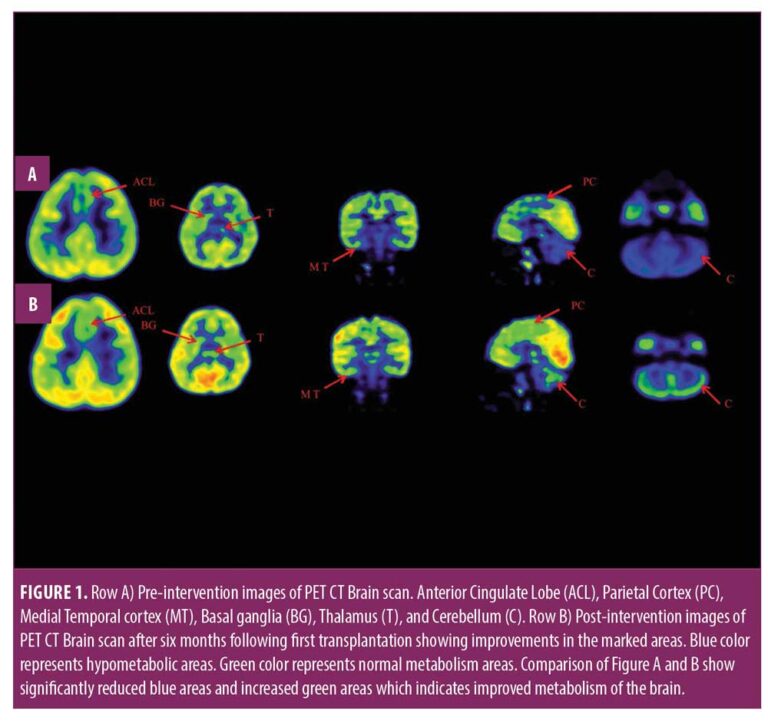

在認知上,由于他定期上學(xué),他的注意力持續時(shí)間和坐姿耐受力也得到了改善。GMFM分數從60.67提高到67。GMFCS等級由3級提升至2級;FIM評分從97分提高到99分。比較第一次細胞治療之前和之后7個(gè)月期間進(jìn)行的腦部PET CT掃描結果,發(fā)現前扣帶回葉、頂葉皮層、內側顳葉皮層、丘腦、基底神經(jīng)節和小腦(表1)。

這項研究表明,多種干細胞療法結合神經(jīng)康復可有效改善腦癱患者的粗大運動(dòng)功能和功能獨立性。自體BMMNC多次移植后進(jìn)行強烈的神經(jīng)康復可加快神經(jīng)再生過(guò)程,這反過(guò)來(lái)又反映了患者殘疾程度和生活質(zhì)量的積極結果。PET CT掃描可以有效地用于監測干預后細胞水平發(fā)生的變化。因此,多細胞療法是安全、可行的,并且可以有效地與腦癱的神經(jīng)康復相結合作為增強治療。